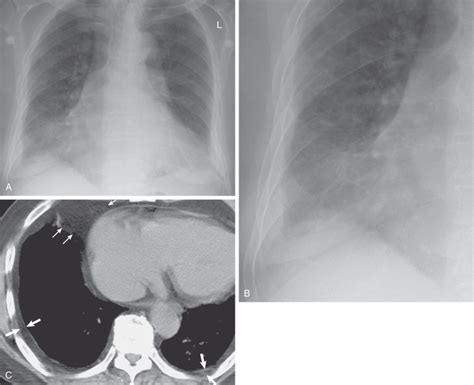

The Role of X-Rays in Diagnosing Mesothelioma

An X-ray is often one of the first imaging tests a doctor orders when there's concern about lung issues or potential asbestos-related diseases. It's a quick, non-invasive way to get a general overview of your lungs and chest cavity. While an X-ray can't definitively diagnose mesothelioma, it can reveal tell-tale signs that warrant more detailed investigation.

Specifically, an X-ray might reveal:

- Evidence of diffuse pleural thickening

- Presence of pleural plaques, which are calcified areas on the pleura

- Pleural effusions, which are fluid build-ups around the lungs

What an X-Ray Might Show: Signs to Look For

When a radiologist reviews your X-ray for Mesothelioma X Ray Pleural Thickening, they are looking for specific patterns. These patterns can indicate asbestos exposure and, in some cases, the presence of mesothelioma. It's important to remember that these are indicators, not final diagnoses.

Diffuse Pleural Thickening on X-Ray

This refers to widespread scarring of the pleura, which can be seen as a haziness or thickening along the lung margins on an X-ray. It's a common finding in individuals with a history of asbestos exposure and can sometimes be a precursor or co-occurrence with mesothelioma. It can restrict lung expansion and cause breathing difficulties.

Pleural Plaques: A Common Indicator

Pleural plaques are well-defined, localized areas of fibrosis and calcification on the outer lining of the lung. They are the most common radiological sign of past asbestos exposure. While plaques themselves are benign and typically do not become cancerous, their presence strongly indicates significant asbestos exposure, which is the primary cause of mesothelioma.

- CT Scans (Computed Tomography): These provide cross-sectional images, offering much more detail than an X-ray about the extent and nature of any thickening or masses.